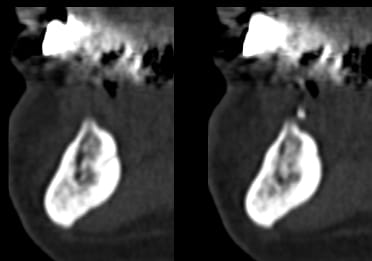

> La démo super bien menée sur un cas bcp plus difficile à gérer

> qu'il y paraissait

> Beaucoup de calme et de sureté et d'humour,dans les moments difficiles et il y

> en a eu, même avec la technique d'expansion condensation les 2 artérioles ont

> essayé de l'embêter, les tables vesti en regard 42 et 32 aussi

> au final 4 implants enfouis et bloqués

> travail très propre et j'ai beaucoup appris

mais je n'aurai du ecouter que mon coeur et en mettre un 5° en 33 ce serait plus joli sur le pano

Le pano pré-op est-il disponible ?

Il y avait des exo ?

C'est quoi le plan de tx pour la prothèse ?

Pourquoi expansion ?

Je crois que la disposition des implants est un peu étrange...